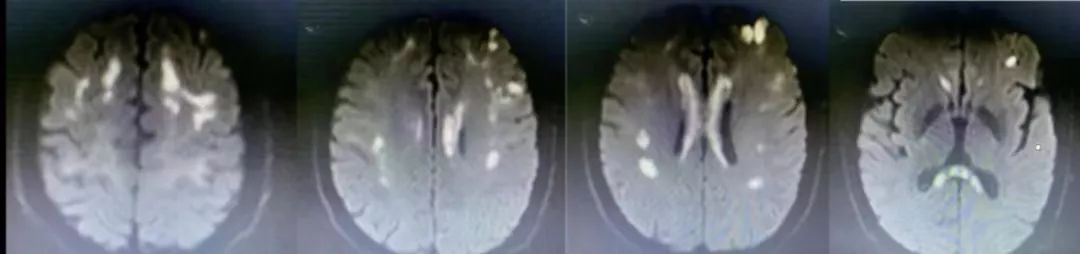

病例13

中年男性,言语障碍10天,一过性意识不清、肢体抽搐8小时。

答案:原发性胼胝体变性。

患者长期酗酒史,补充维生素B1后症状明显改善。Marchiafava-Bignami病又称原发性胼胝体变性,是一种以累及胼胝体及邻近脑白质为主的脱髓鞘性疾病,多见于慢性酒精中毒及营养不良患者,多数学者认为本病与慢性酒精中毒、营养不良有关,也有非酒精中毒的个例报道。MBD主要病理改变是胼胝体脱髓鞘和坏死,病灶分布一胼胝体为中心,向上累及半球白质、皮质,向下累及内囊、前连合、桥臂等,起病形式分为三种类型:急性型、亚急性型、慢性型,三种起病形式均累及胼胝体。大脑半球白质是MBD最易累及的胼胝体外区域,桥臂也是MBD较易累及的胼胝体外区域。MBD急性期胼胝体肿胀,CT表现为低密度,MRI表现为胼胝体对称性长T1、长T2信号,DWI呈高信号,ADC可呈现低信号、等或高信号,在亚急性期,胼胝体肿胀程度逐渐减轻,亚急性及慢性期可出现胼胝体中层信号异常,而腹侧、背侧结构完好,呈“三明治”夹层状改变。